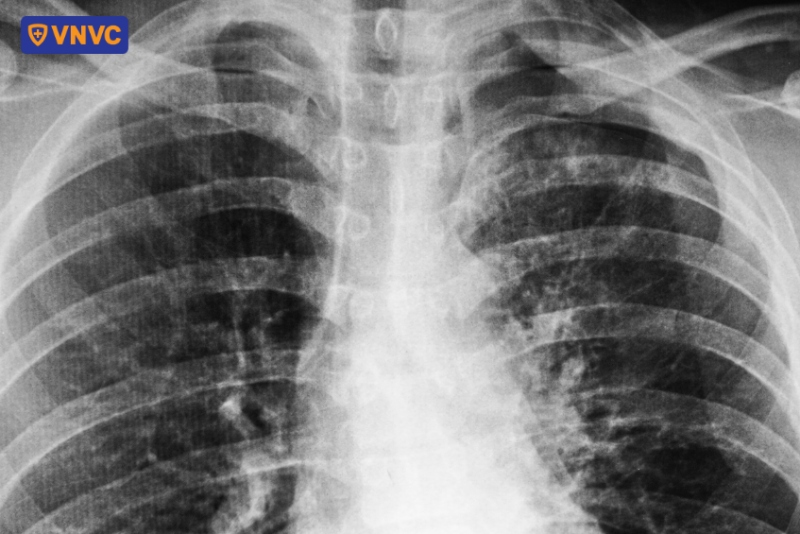

Hướng dẫn đọc chẩn đoán qua hình ảnh X quang viêm phế quản

Đọc hình ảnh X quang viêm phế quản đòi hỏi sự hiểu biết về các đặc điểm hình ảnh đặc trưng của từng loại viêm phế quản, cụ thể như sau:

1. Hình ảnh chẩn đoán viêm phế quản cấp

Viêm phế quản cấp thường gây ra bởi virus hoặc vi khuẩn, dẫn đến viêm niêm mạc phế quản mà không gây tổn thương nhu mô phổi. Do đó, trong viêm phế quản cấp, X quang thường bình thường hoặc chỉ có những thay đổi nhẹ, không có tổn thương đông đặc điển hình.

Hình ảnh chụp X quang viêm phế quản cấp tính giúp bác sĩ có thể loại trừ viêm phổi hoặc phân biệt với các bệnh lý lao phổi, phù phổi hoặc bệnh phổi tắc nghẽn mạn tính (COPD). Ngoài ra, bác sĩ cũng có thể đánh giá biến chứng bội nhiễm hoặc tiến triển của bệnh để có hướng điều trị kịp thời.

2. Ảnh chẩn đoán viêm phế quản mạn

Viêm phế quản mạn là tình trạng viêm kéo dài, thường liên quan đến hút thuốc lá hoặc tiếp xúc lâu dài với các yếu tố gây kích ứng. Trên X quang, các dấu hiệu bao gồm:

- Dày thành phế quản rõ rệt: Thành phế quản dày hơn so với viêm phế quản cấp, cho thấy tình trạng viêm kéo dài

- Tăng đậm vân phổi: Vân phổi dày hơn do tăng tiết nhầy.

- Hình ảnh khí phế thũng: Ở một số bệnh nhân, có thể thấy dấu hiệu khí phế thũng hoặc phổi bị căng phồng.

- Bóng tim to: Đặc biệt là thất phải, có thể kèm theo dấu hiệu sung huyết phổi hoặc tràn dịch màng phổi.

3. Hình X quang viêm tiểu phế quản

Viêm tiểu phế quản thường gặp ở trẻ em, đặc biệt là trẻ dưới 1 tuổi và thường do virus hợp bào hô hấp (RSV) gây ra. Trên X quang, các dấu hiệu viêm tiểu phế quản thường được biểu hiện mờ các tiểu phế quản, đôi khi xẹp cục bộ hoặc toàn bộ phân thùy do bít tắc cùng các bùng ứ khí đặc trưng bởi tình trạng tăng sáng.